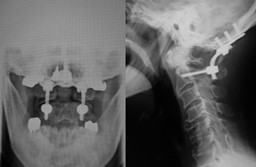

図 頭蓋底陥入症

(左)第2頚椎歯突起が頭蓋骨内に陥入し、延髄と脊髄を圧迫している。

(右)手術により神経の圧迫は解除されている